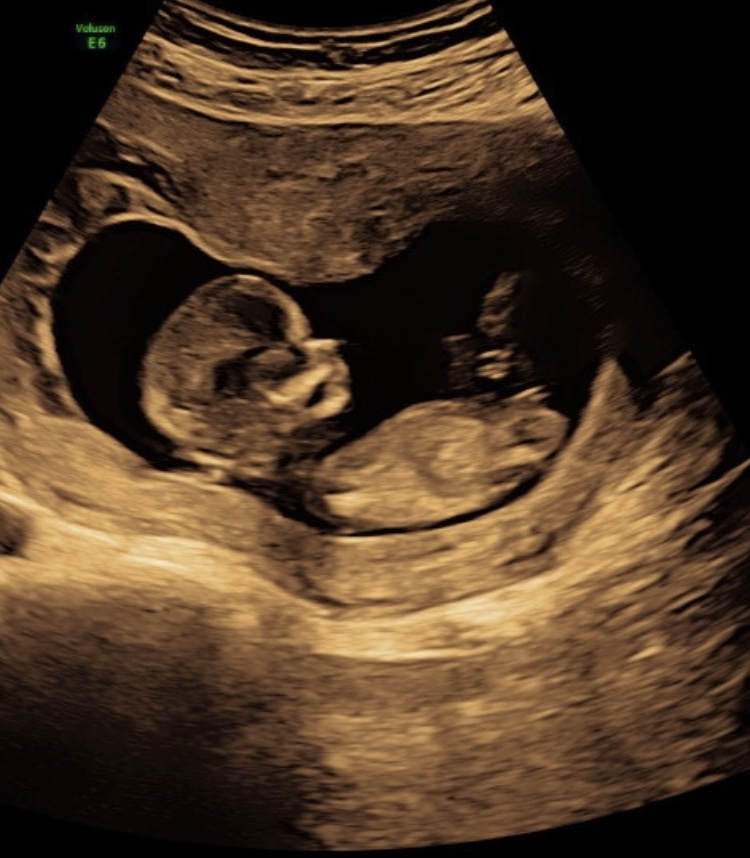

Is this a boy or a girl nub? I think it is a decent nub shot but not really sure.Attachment 41357